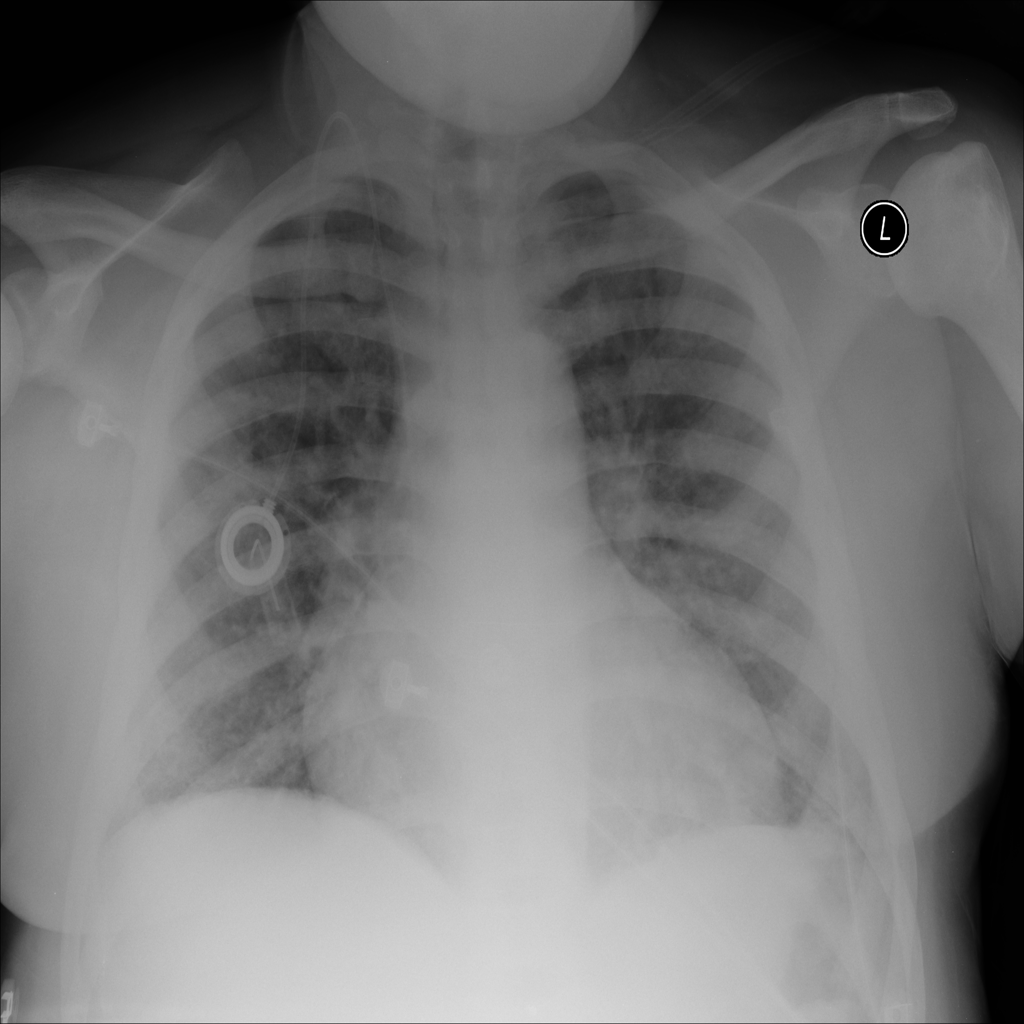

PAT-B3C3 · IMG-001Pneumonia

PAT-B3C3 · IMG-001

PA